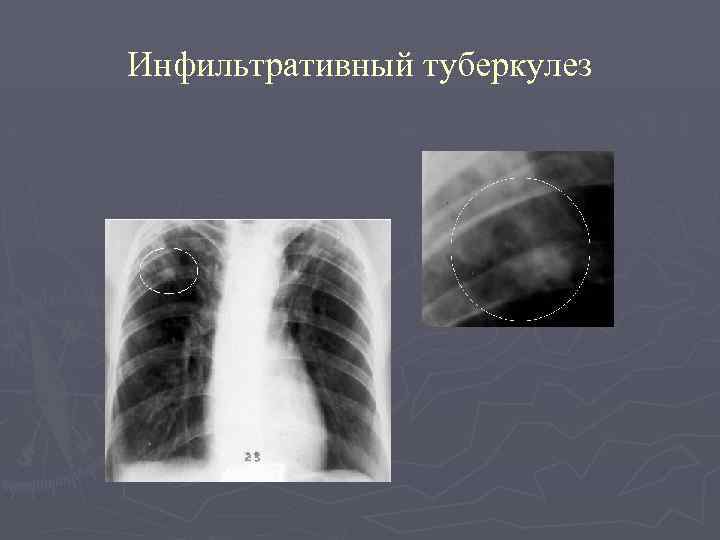

Иллюстрации по теме очагового и инфильтративного туберкулеза